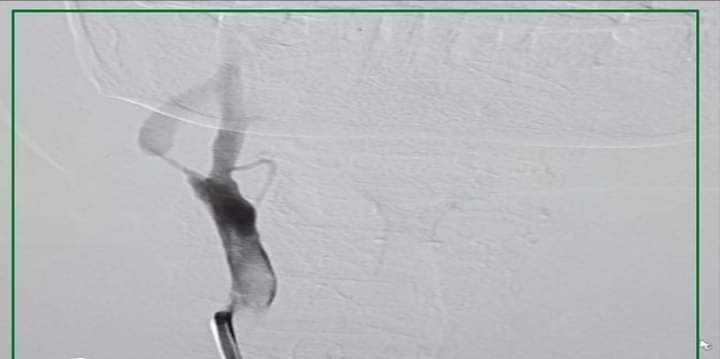

وأضاف الدكتور إسلام المالكي الأستاذ المساعد بقسم النفسية والعصبية بطب قنا أن القسم استقبل المريضة التي تبلغ 67 عامًا مصابة بجلطة مخية، وبالكشف والفحص الطبي والاستعلام عن التاريخ المرضي، تبين أن المريضة تعاني من جلطات مخية متكررة وجلطة بالمخ وضيق بالشريان السباتي الأيمن بنسبة تعدت 90%، مما تتطلب التدخل بالقسطرة المخية من خلال فريق طبي من القسم تحت إشراف الدكتور طارق دسوقي البجع، رئيس القسم، حيث تم إجراء قسطرة مخية علاجية دقيقة للمريضة بنجاح وتركيب دعامة شريانية للشريان السباتي.

يذكر أن الفريق الطبي المعالج بقيادة الدكتور إسلام المالكي ضم الدكتور محمود عبد الحافظ المدرس بالقسم وبمشاركة فني الأشعة والتمريض بالقسم.